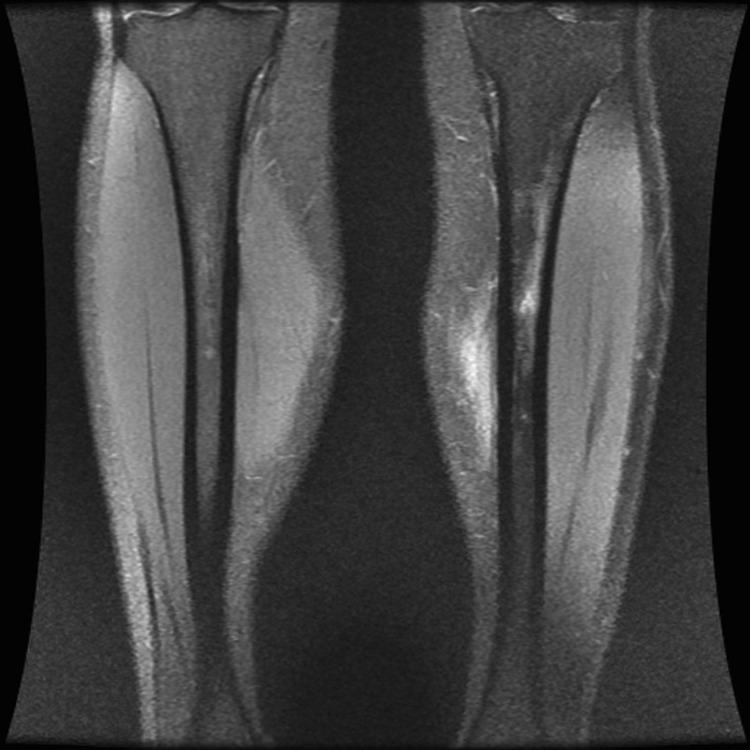

Leg pain in athletes can be caused by many conditions, with the most frequent being medial tibial stress syndrome; chronic exertional compartment syndrome, stress fracture, nerve entrapment, and popliteal artery entrapment syndrome are also considerations. Conservative management is the mainstay of care for the majority of causes of chronic lower leg pain; however, surgical intervention may be necessary.

Chronic lower extremity pain in athletes includes a wide differential and can pose diagnostic dilemmas for clinicians.